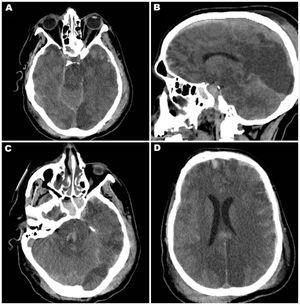

El segundo paciente, varón de 40 años, fue derivado tras un accidente vehicular. Ingresó con Glasgow 6 e intubación orotraqueal. Estaba bajo asistencia respiratoria mecánica, sin fármacos sedativos, con pupilas midriáticas arreactivas, ausencia de reflejos vestibuloculares, corneanos, cilioespinales y respuesta motora al dolor, solo con reflejo tusígeno mantenido. La TC de cráneo mostró desviación de línea media de 6mm, contusiones hemorrágicas bifrontales y temporales, hemorragia subaracnoidea difusa, hematoma subdural laminar izquierdo, edema cerebral posterior con colapso de cisternas peritroncales y foco hemorrágico en protuberancia, compatibles con herniación central y hemorragias de Duret. Tras una prueba de apnea positiva, se diagnosticó muerte encefálica y se activó el protocolo de donación de órganos (fig. 2).